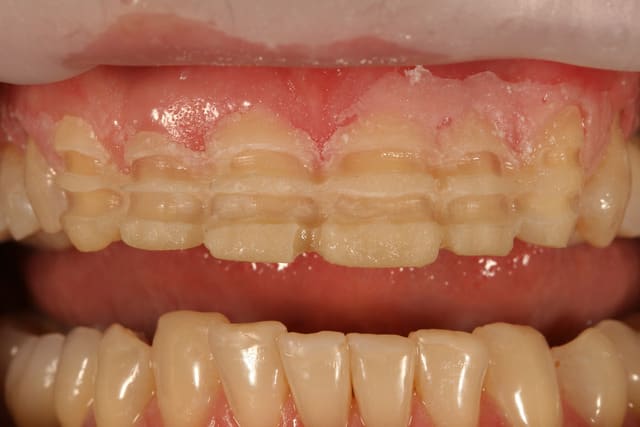

enfin un cas sympa pour faire des facettes, et a part une unitaire une fois c'est mon premier cas

le premier mock up était tout penché un peu plat, j'ai rajouté du composite par dessus la cire pour en faire un second qui nous plaise plus, à la patiente et à moi.

on a pas voulu toucher le collet de la 12, patiente pas motivée pour chir et ça me simplifiait la vie pour une première

ce sont des emax qui sont prévues

essayage, et comme on peut le voir sur la première photo, c'est bizarement long par rapport au provisoire ...

pourtant le prothésiste avait un alginate des mocks-up

j'ai mis du sealtemp et essayé tout ça, c'est trop long

par contre, je me dis que je suis resté trop supra-gingival sur mes préparations, ça se voit trop, même si la patiente découvre peu, elle découvre un peu et j'aurais du aller plus juxta.